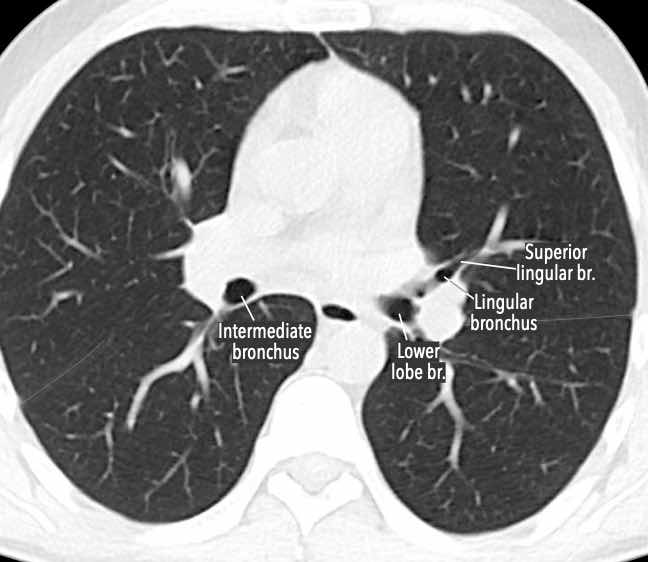

Phế quản trên CT

Cuộn qua các hình ảnh để quan sát khí quản phân chia thành phế quản chính phải và trái, sau đó tiếp tục phân chia thành các phế quản thùy và phế quản phân thùy.